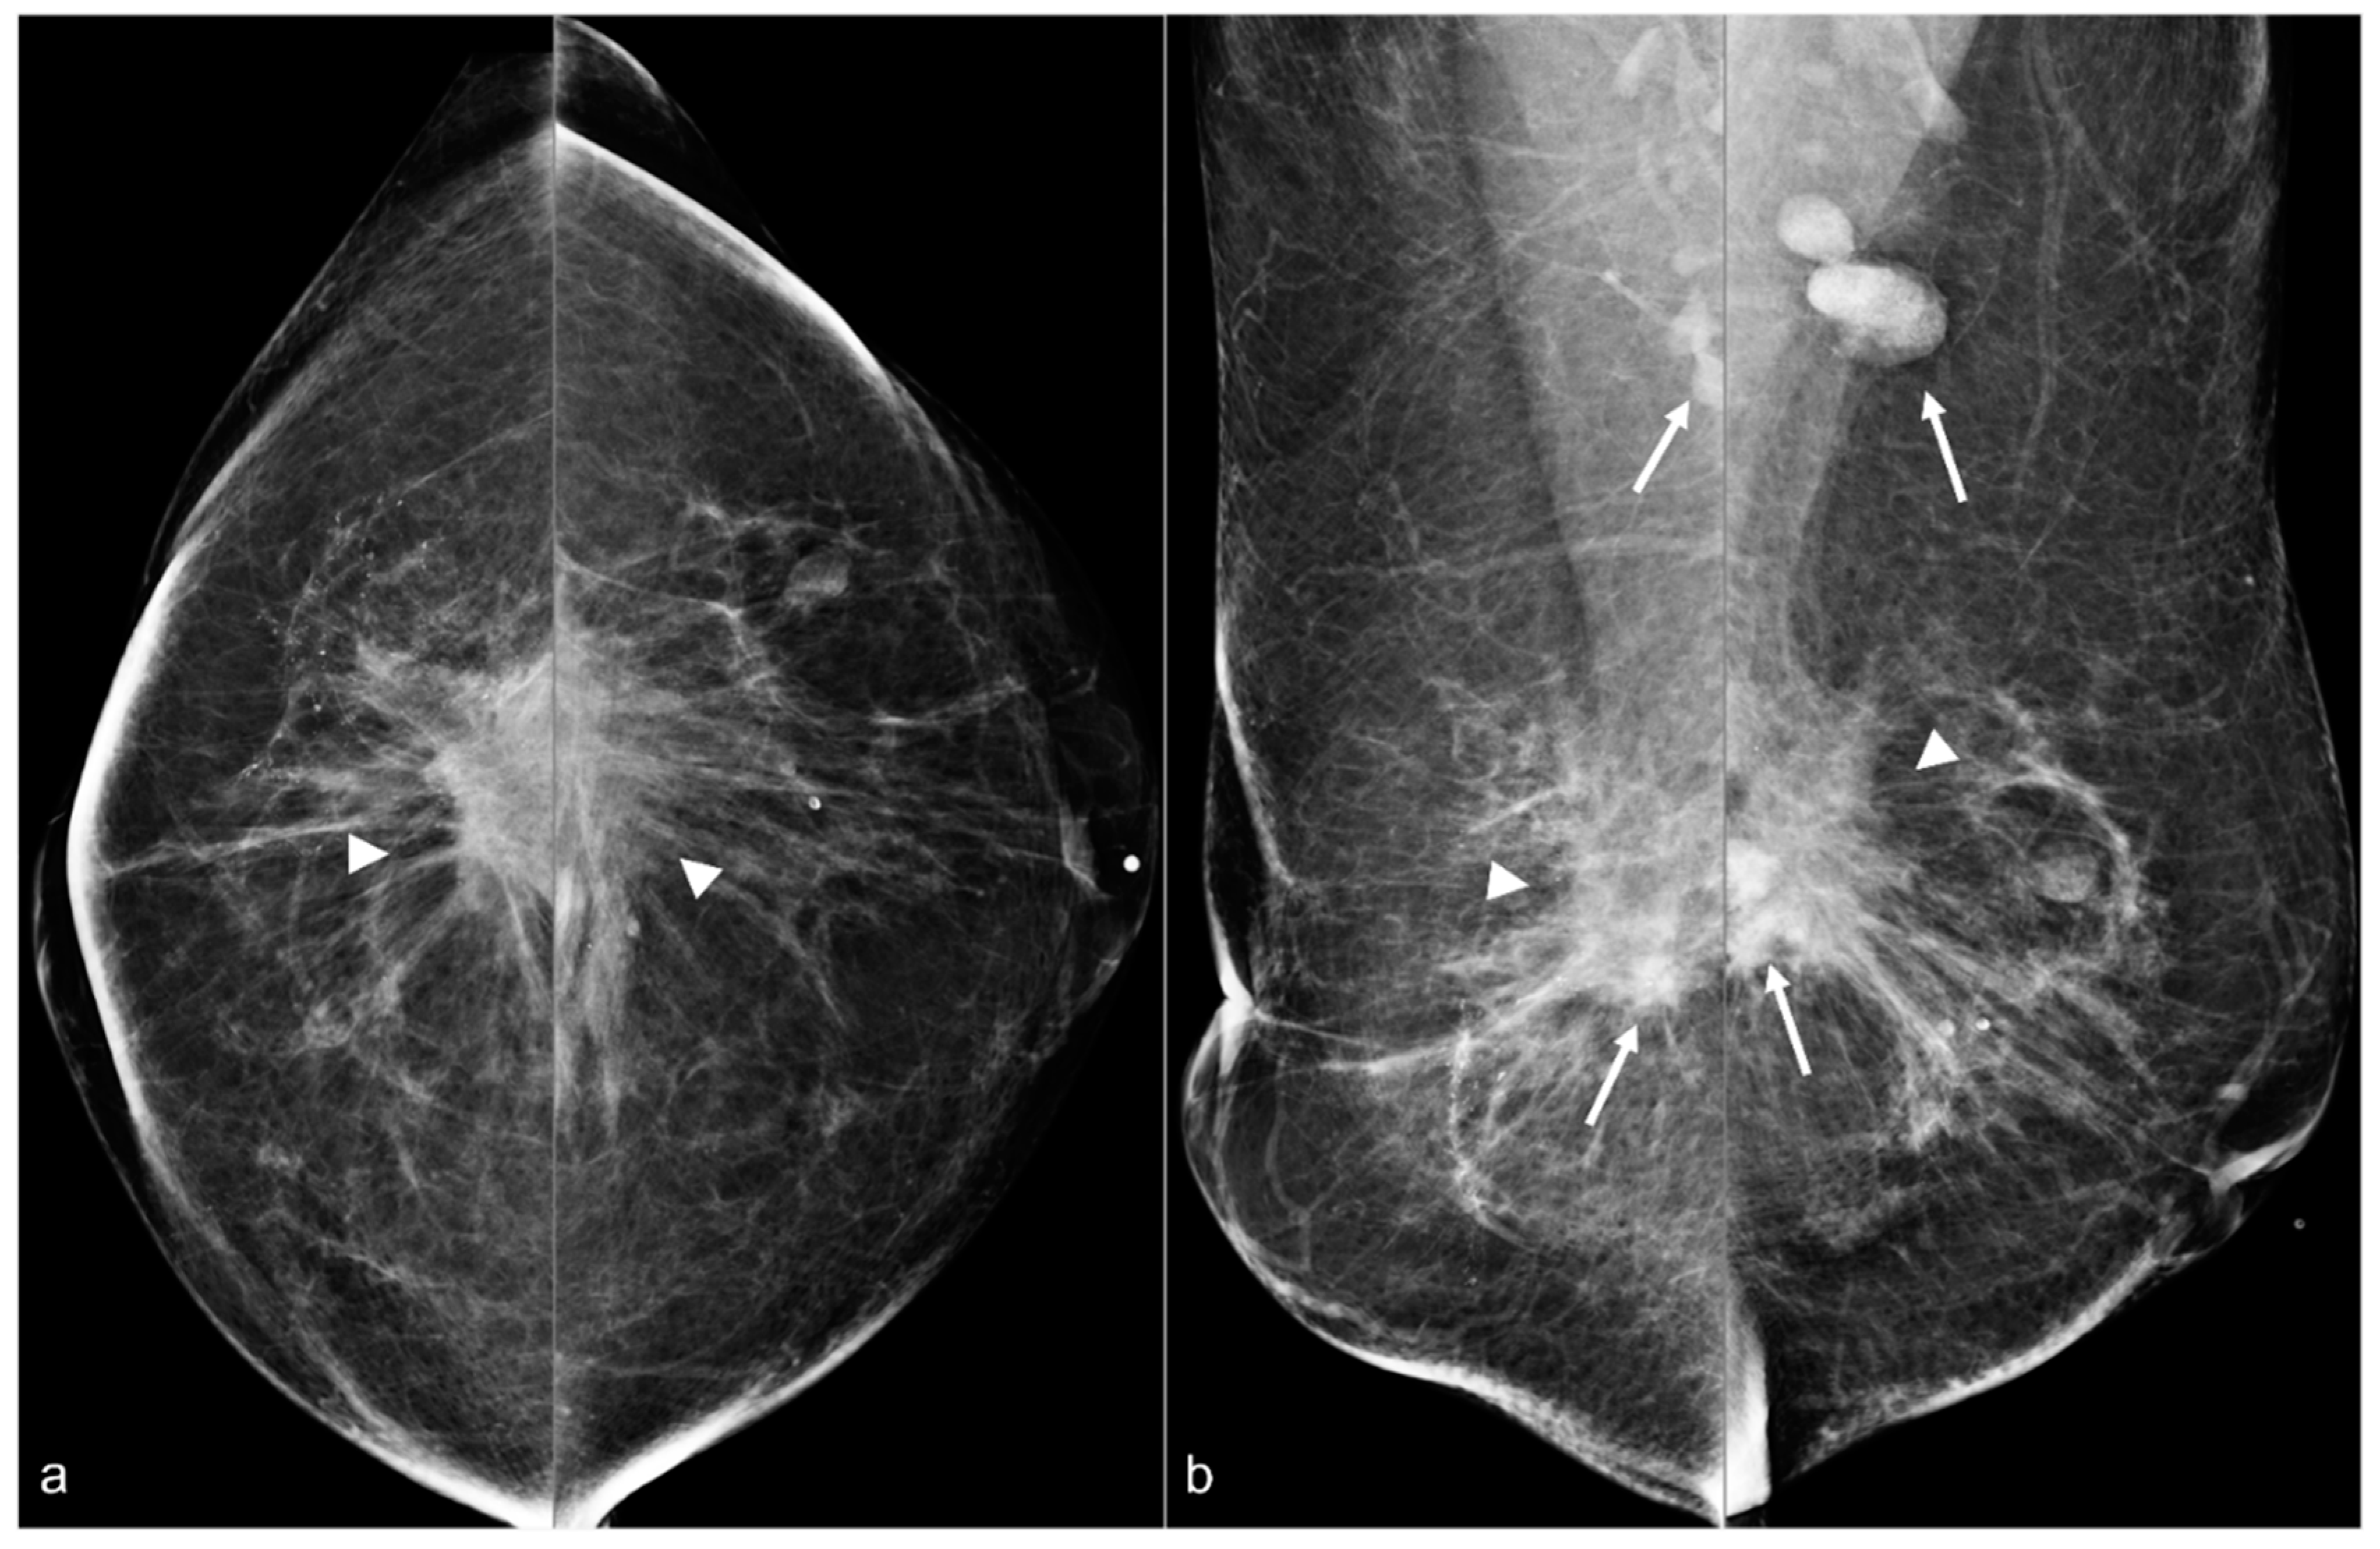

Figure 11. A 67-year-old woman with a history of subglandular silicone implants. Mammograms with bilateral CC (a) and MLO (b) views demonstrate curvilinear densities (arrows), consistent with residual implant capsules.